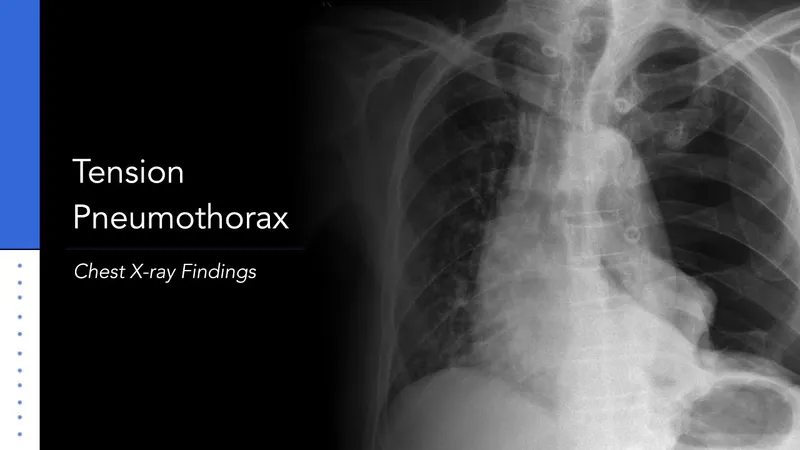

- Tension Pneumothorax: Needle decompression (e.g., 14-16G needle, 2nd ICS MCL), then chest tube (5th ICS MAL).

⭐ In tension pneumothorax, clinical diagnosis trumps radiological confirmation for immediate needle decompression.

- Tension Pneumothorax: Clinical Dx (hypotension, JVD, ↓breath sounds, tracheal shift).

- Immediate needle decompression (2nd ICS MCL / 5th ICS AAL), then chest tube.

- Anesthesia: 100% O2. Avoid N2O. Positive Pressure Ventilation (PPV) worsens pre-decompression.

- Tension pneumothorax requires immediate needle decompression, followed by chest tube insertion.